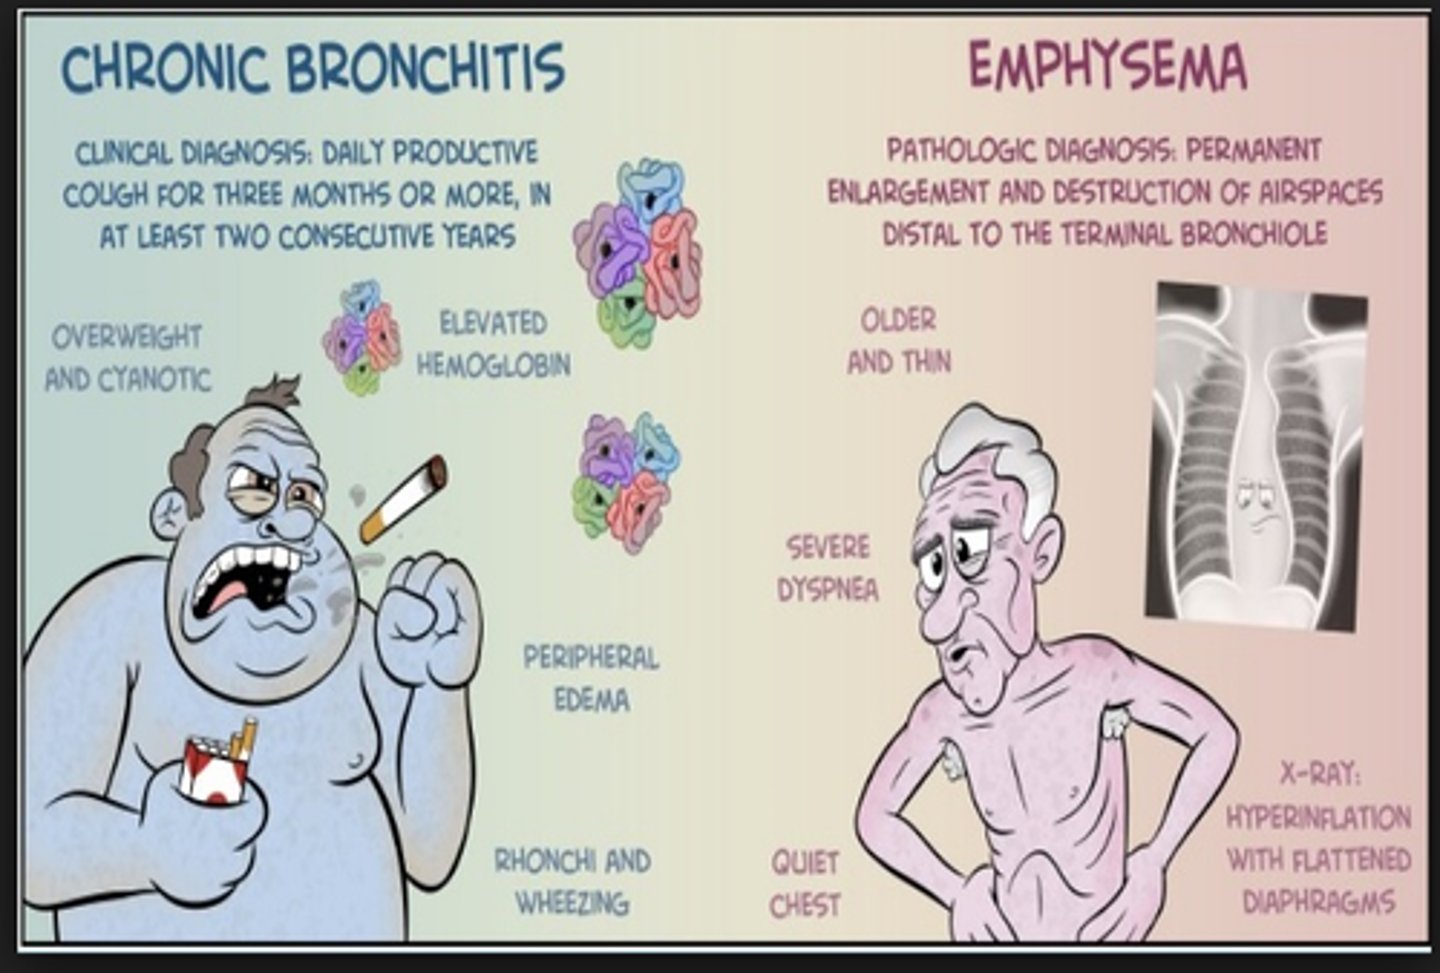

Hypoxemia, polycythemia, hypercapnia

"Blue bloater"

(chronic bronchitis: hyperplasia of mucous cells)

Clinical diagnosis from productive cough in 3+ months in at least 2 consecutive years

Pink complexion, dyspnea, hyperventilation

"Pink puffer" (emphysema: centracinar [smoking], panacinar [alpha-1 antitrypsin deficiency])

![<p>"Pink puffer" (emphysema: centracinar [smoking], panacinar [alpha-1 antitrypsin deficiency])</p>](https://knowt-user-attachments.s3.amazonaws.com/69972a2c-dba6-4040-8fe7-3df0c5688084.jpg)